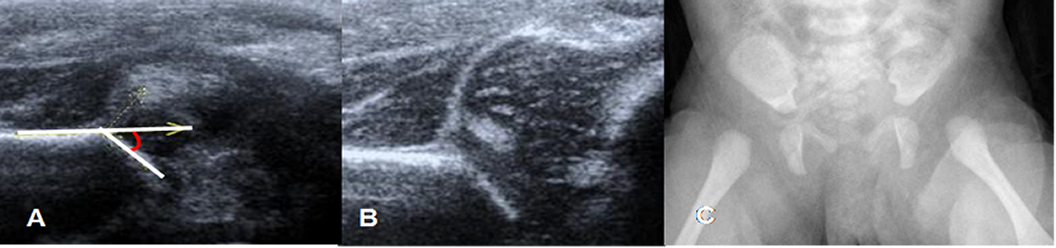

Fig 33 B. Displasia de cadera.

Ecografía. A: Disminución del ángulo alfa (50º) y B: Disminución de la relación A/B, por displasia.

Fig 34. Displasia de cadera.

A y B: Ecografía. Disminución del ángulo alfa (43º), por displasia. En B hay desplazamiento superior de la cabeza femoral, por luxación.

C: Rx AP. El mismo paciente con imposibilidad para completa extensión de los muslos. Existe desplazamiento lateral de ambas cabezas femorales, secundario a luxación.